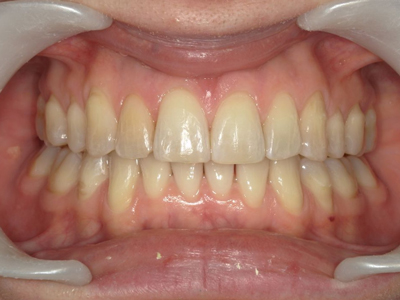

Présentation cas n°2 :